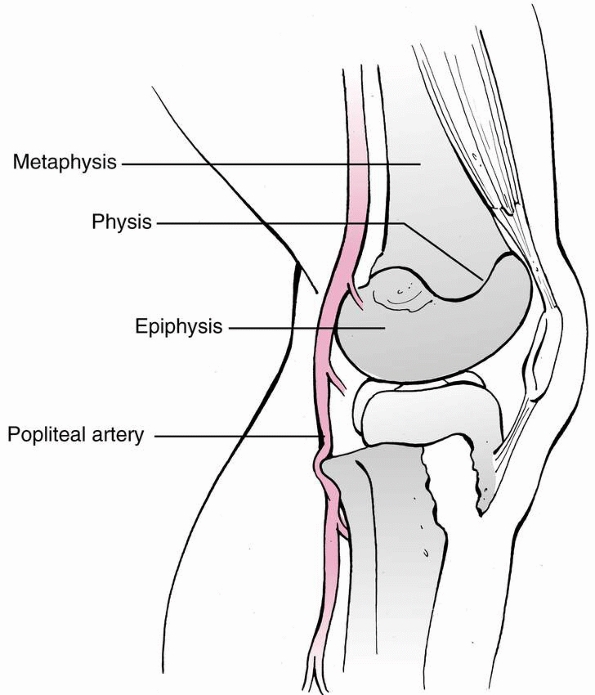

The popliteal artery is tethered by its major branches near the

posterior surface of the proximal tibial epiphysis. The posterior

tibial branch passes under the arching fibers of the soleus. The

anterior tibial artery travels anteriorly over an aperture above the

proximal border of the interosseous membrane. A hyperextension injury

that results in posterior displacement of the proximal tibial

metaphysis may stretch and tear the tethered popliteal artery (Figs. 23-17 and 23-18).

![]() |

FIGURE 23-17

Posterior displacement of the epiphysis following fracture-separation at the time of injury can cause arterial injury. In addition, a posteriorly displaced fragment can cause persistent arterial occlusion by direct pressure. (Reprinted with permission from Skaggs DL, Flynn JF. Trauma about the knee, tibia, and foot. In Skaggs DL, Flynn JF, eds. Staying out of Trouble in Pediatric Orthopaedics. Philadelphia: Lippincott Williams & Wilkins; 2006.) |